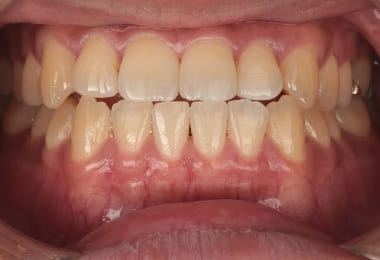

Before

2週間後

After